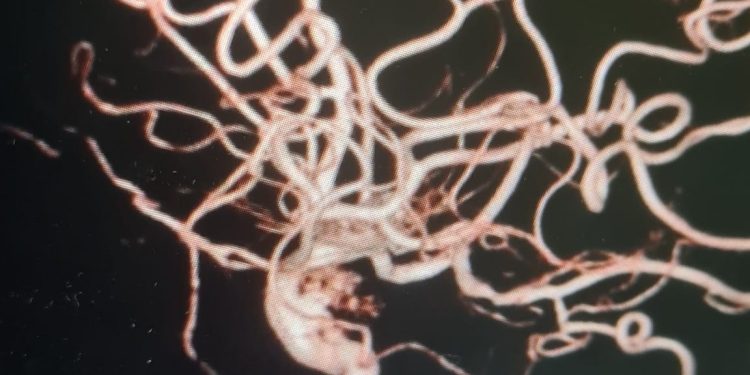

Hình ảnh túi phình mạch não chụp DSA

Bệnh nhân được chỉ định chụp mạch máu não số hóa xóa nền, với kết quả:

-Túi phình ĐMC đoạn xoang hang kích thước 4.6 x 3.4 mm, bờ nham nhở có nhú.

-Túi phình ĐMC cảnh đoạn xoang hang kích thước 15 x 13 x 4.6mm, bờ tròn đều. Sau khi hội chẩn với chuyên gia can thiệp nội mạch thần kinh của Bệnh viện ĐHYD TP.HCM, cân nhắc các yếu tố về kích thước, vị trí, hình thái học của túi phình. Êkip đã quyết định điều trị túi phình lớn bên trái bằng phương pháp can thiệp nội mạch gồm: stent chuyển dòng và coilling một phần túi phình nhằm ngăn ngừa túi phình vỡ.